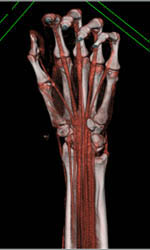

Plasmacytoma